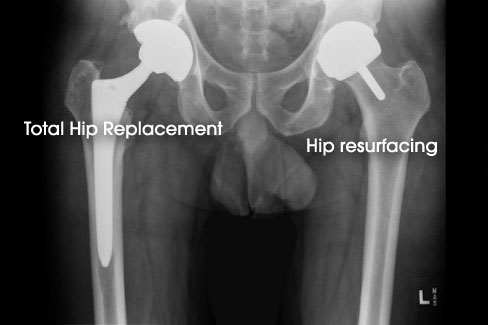

In Total Hip Replacement (THR), the ball and socket of the hip joint are replaced. The femoral head is removed, and a stemmed component is placed into the central part of the upper thigh bone (see Figure 1).

Hip resurfacing is similar although instead of removing the femoral head completely, only the damaged cartilage and a small amount of bone is removed, and a metal cap is placed on top (see Figure 2).